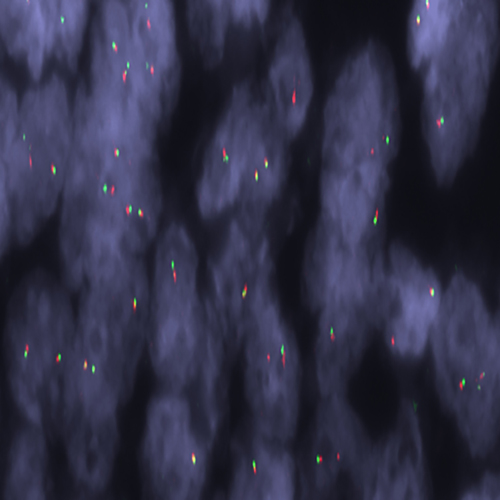

Liposarcoma stained using FUS (16p11) Break – XL for BOND (KBI-XL017).

The FUS (16p11) Break - XL for BOND FISH probe detects genomic translocations involving the FUS gene. FUS (16p11) Proximal - XL and FUS (16p11) Distal - XL are optimized to detect genomic regions proximal and distal to break points in the FUS gene region.

When combined, both probes are used to detect translocations involving the FUS gene at 16p11.